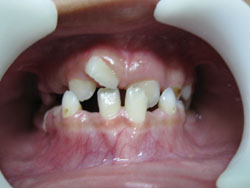

- *Răng mọc chen chúc:

- Răng mọc chen chúc là tình trạng các răng sắp xếp lộn xộn, không ngay ngắn trên cung hàm , răng mọc không đều, các răng khấp khểnh do thiếu chỗ (răng quá to hay xương hàm cung răng quá nhỏ không đủ chỗ để các răng sắp xếp).